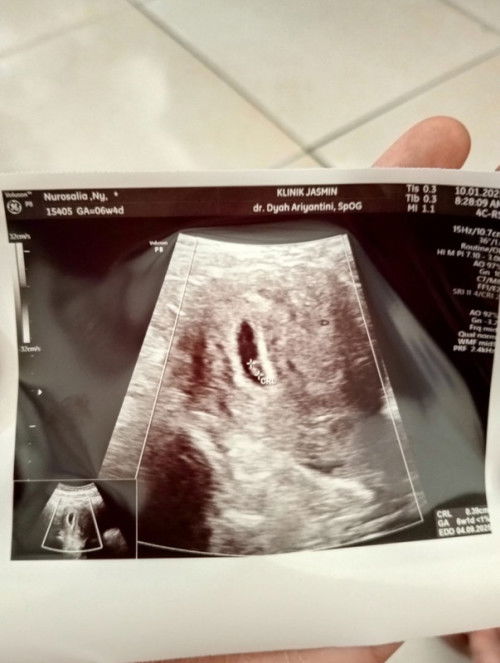

Hasil USG 2D di tgl 10 Januari 2025 💞 Usia 6 Minggu kata dr.SpoG masih sangat kecil janinnya 💞 Penantian 7thn anak pertama ya Bun 🥰, sebelumnya pernah ada riwayat Keguguran di thn 2021 Alhamdulillah sekarang di awal tahun 2025 diberi hadiah terindah & lepas sebagai pejuang Garis 2 😍, dan pernah jg promil di dr.SpoG selama 2 bln (OKTOBER-NOVEMBER) sudah sampai tahap'an HSG (SUDAH DAPAT SURAT RUJUKAN KE RADIOLOGI) tp sampai sekarang belum saya lakukan karna memang mental belum siap🥹, puji syukur Alhamdulillah belum melakukan HSG sampai sekarang akhirnya diberi anugerah terindah di awal tahun 2025 🥹🥰💞 Perkiraan HPL di tgl "2 SEPTEMBER 2025" mohon doanya ya Bun 🥰, semoga Debay sehat² sampai menjelang HPL hingga Melahirkan Normal & Sehat nantinya 🤲😇 #Sharingdong_Bund #sharing #firstmom